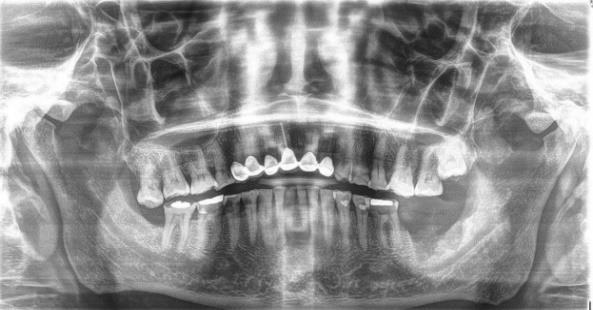

Presentación de caso clínico

Paciente masculino de 63 años de edad, presenta lesión en reborde alveolar

zona de segundo y tercer molar inferior, eritematosa, de forma irregular, de bordes elevados, consistencia blanda que se desprende fácilmente, causa dolor persistente a la manipulación con presencia de sangrado a la palpación y exudado. (Fig.10) de 2 meses de evolución, ha sido tratado con agua oxigenada y tratamientos caseros sin mejoría, con antecedentes de tabaquismo y alcohol. A la exploración radiográfica se aprecia lesión radiolúcida maldelimitada(Fig.11).

Fig. 11

Ortopantomografía; lesión radiolúcida mal delimitada localizada en tercer cuadrante, autoría propia.

Nota:FotocortesíaDra.JazmínFuentesMarroquín